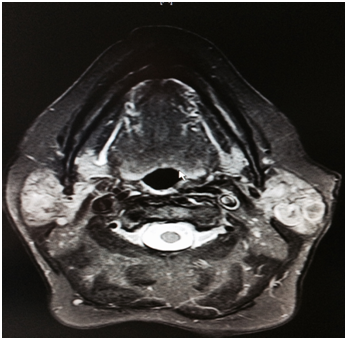

An 80-year-old Caucasian woman presented in our ENT department due to a progressive swelling on the left parotid gland during a period of two months. The physical examination showed a soft and mobile mass on the left parotid gland. The flexible fiber optic laryngoscopy showed a mass in the left laryngeal ventricle with intact laryngeal mucosa. The ultrasound of the salivary glands showed a multi - lobular tumor of both left and right parotid glands. The MRI scan showed a 1.2 x 1.1cm solid tumor in the left supraglottic region, without infiltration of adjacent tissues. In the parotid region was a 2.7 x 1.8cm solid mass in the left parotid gland as well as a 0.8 x 1.2cm solid mass in the inferior lobe of the left parotid gland (Figure 1&2). The patient was operated under general anesthesia. The larynx tumor was resected via transoral laser excision and the parotid tumor of the left side was resected via lateral parotidectomy. The histopathological examination showed a cystadenolymphoma that consist of an oncocytic epithelial cell component arranged in double layers, which develops cysts and papillary projections, and a variable amount of lymphoid tissue with germinal centers (Figure 3). An oversupply of lymphoid stroma with a characteristic formation of lymph follicles (Figure 4) was observed in all histological specimens with hematoxylin and eosin stain. There were no granulomas and no evidence of bacterial, fungal, or parasitic infection. The final diagnosis was a cystadenolymphoma in the morgagni sinus as well as multiple lesions in the parotid gland, compatible with a cystadenolymphoma. After consulting the patient, an ultrasound controlled fine needle aspiration of the tumor of the right parotid gland was performed. The histopathological examination showed a cystadenolymphoma of the right parotid gland.